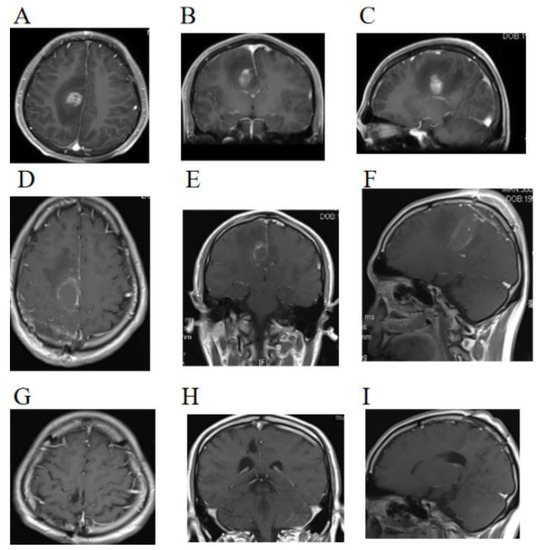

TTFields Prolonged the PFS of Epithelioid Glioblastoma Patient: A Case Report

Epithelioid glioblastoma (EGBM, classified as glioblastoma, IDH wild type, grade 4 according to the fifth edition of the World Health Organization (WHO) Classification of Tumors of the Central Nervous System (CNS) (WHO CNS5)) is a highly aggressive malignancy, with a median progression-free survival [...] Read more.

Epithelioid glioblastoma (EGBM, classified as glioblastoma, IDH wild type, grade 4 according to the fifth edition of the World Health Organization (WHO) Classification of Tumors of the Central Nervous System (CNS) (WHO CNS5)) is a highly aggressive malignancy, with a median progression-free survival (mPFS) of about 6 months in adults. The application of tumor-treating fields (TTFields, possessing anti-cancer capabilities via anti-mitotic effects) in the maintenance of temozolomide (TMZ) chemotherapy showed a benefit for prolonging the mPFS of newly diagnosed glioblastoma (GBM) for patients for up to 6.9 months in the EF-14 clinical trial (NCT00916409). However, studies focusing on the effect of TTFields in EGBM treatment are very limited due to the rarity of EGBM. Here, we have reported a case of a 28-year-old male (recurrent left-sided limb twitching for 1 month and dizziness for 1 week) diagnosed with EGBM. A right frontal lobe occupancy was detected by magnetic resonance imaging (MRI), and a total tumor resection was performed. Meanwhile, a postoperative histopathology test, including immunohistochemistry and molecular characterization, was conducted, and the results revealed a BRAF V600E mutation, no co-deletion of 1p and 19q, and negative O-6-methylguanine DNA methyltransferase (MGMT) promoter methylation. Then, chemoradiotherapy was conducted, and TTFields and TMZ were performed sequentially. Notably, a long-term PFS of 34 months and a Karnofsky Performance Scale (KPS) of 90 were achieved by the patient on TTFields combined with TMZ, whose average daily usage of TTFields was higher than 90%. Full article